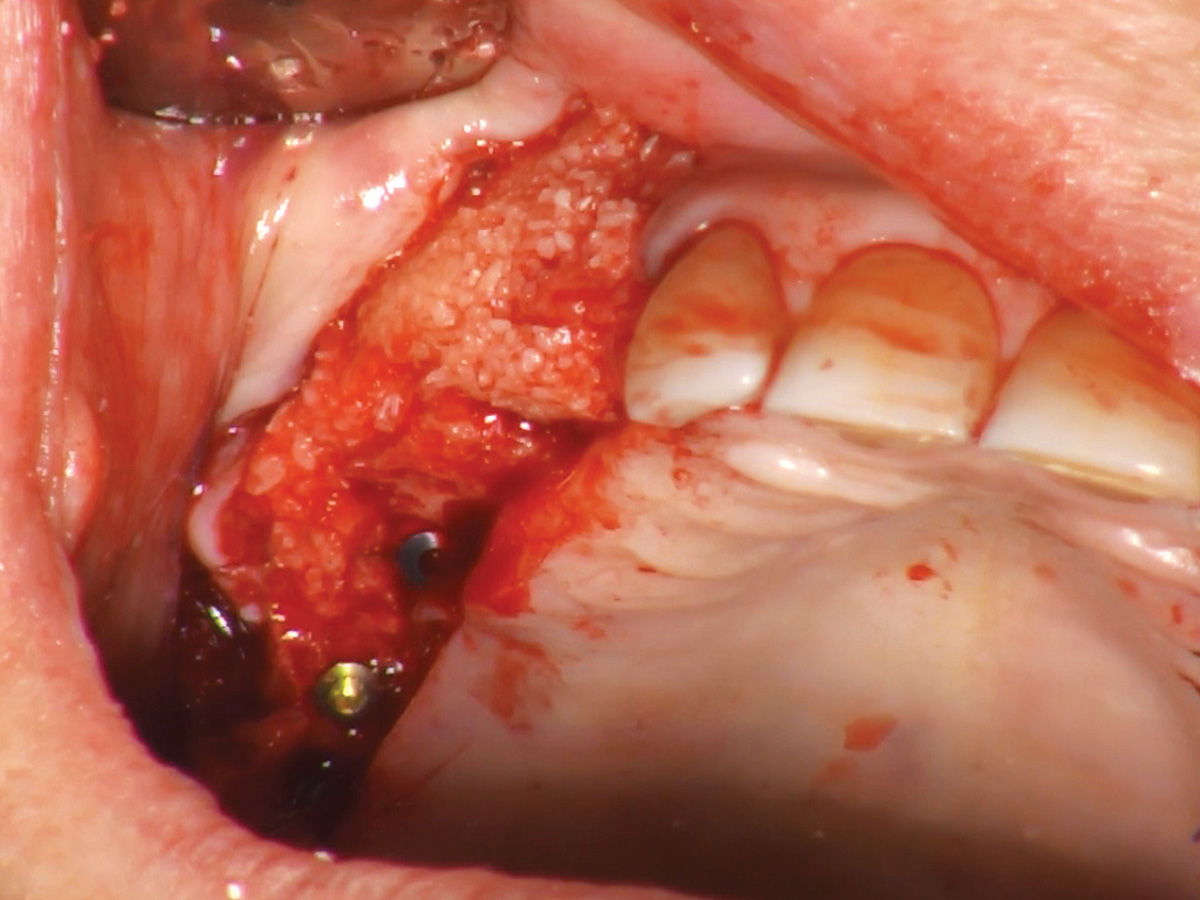

Abbildung 3

Augmentation des Sinusbodens mit OsteoBiol® GTO®.

Abbildung 4

Der Augmentationsbereich ist bereit für die Sofortimplantation.